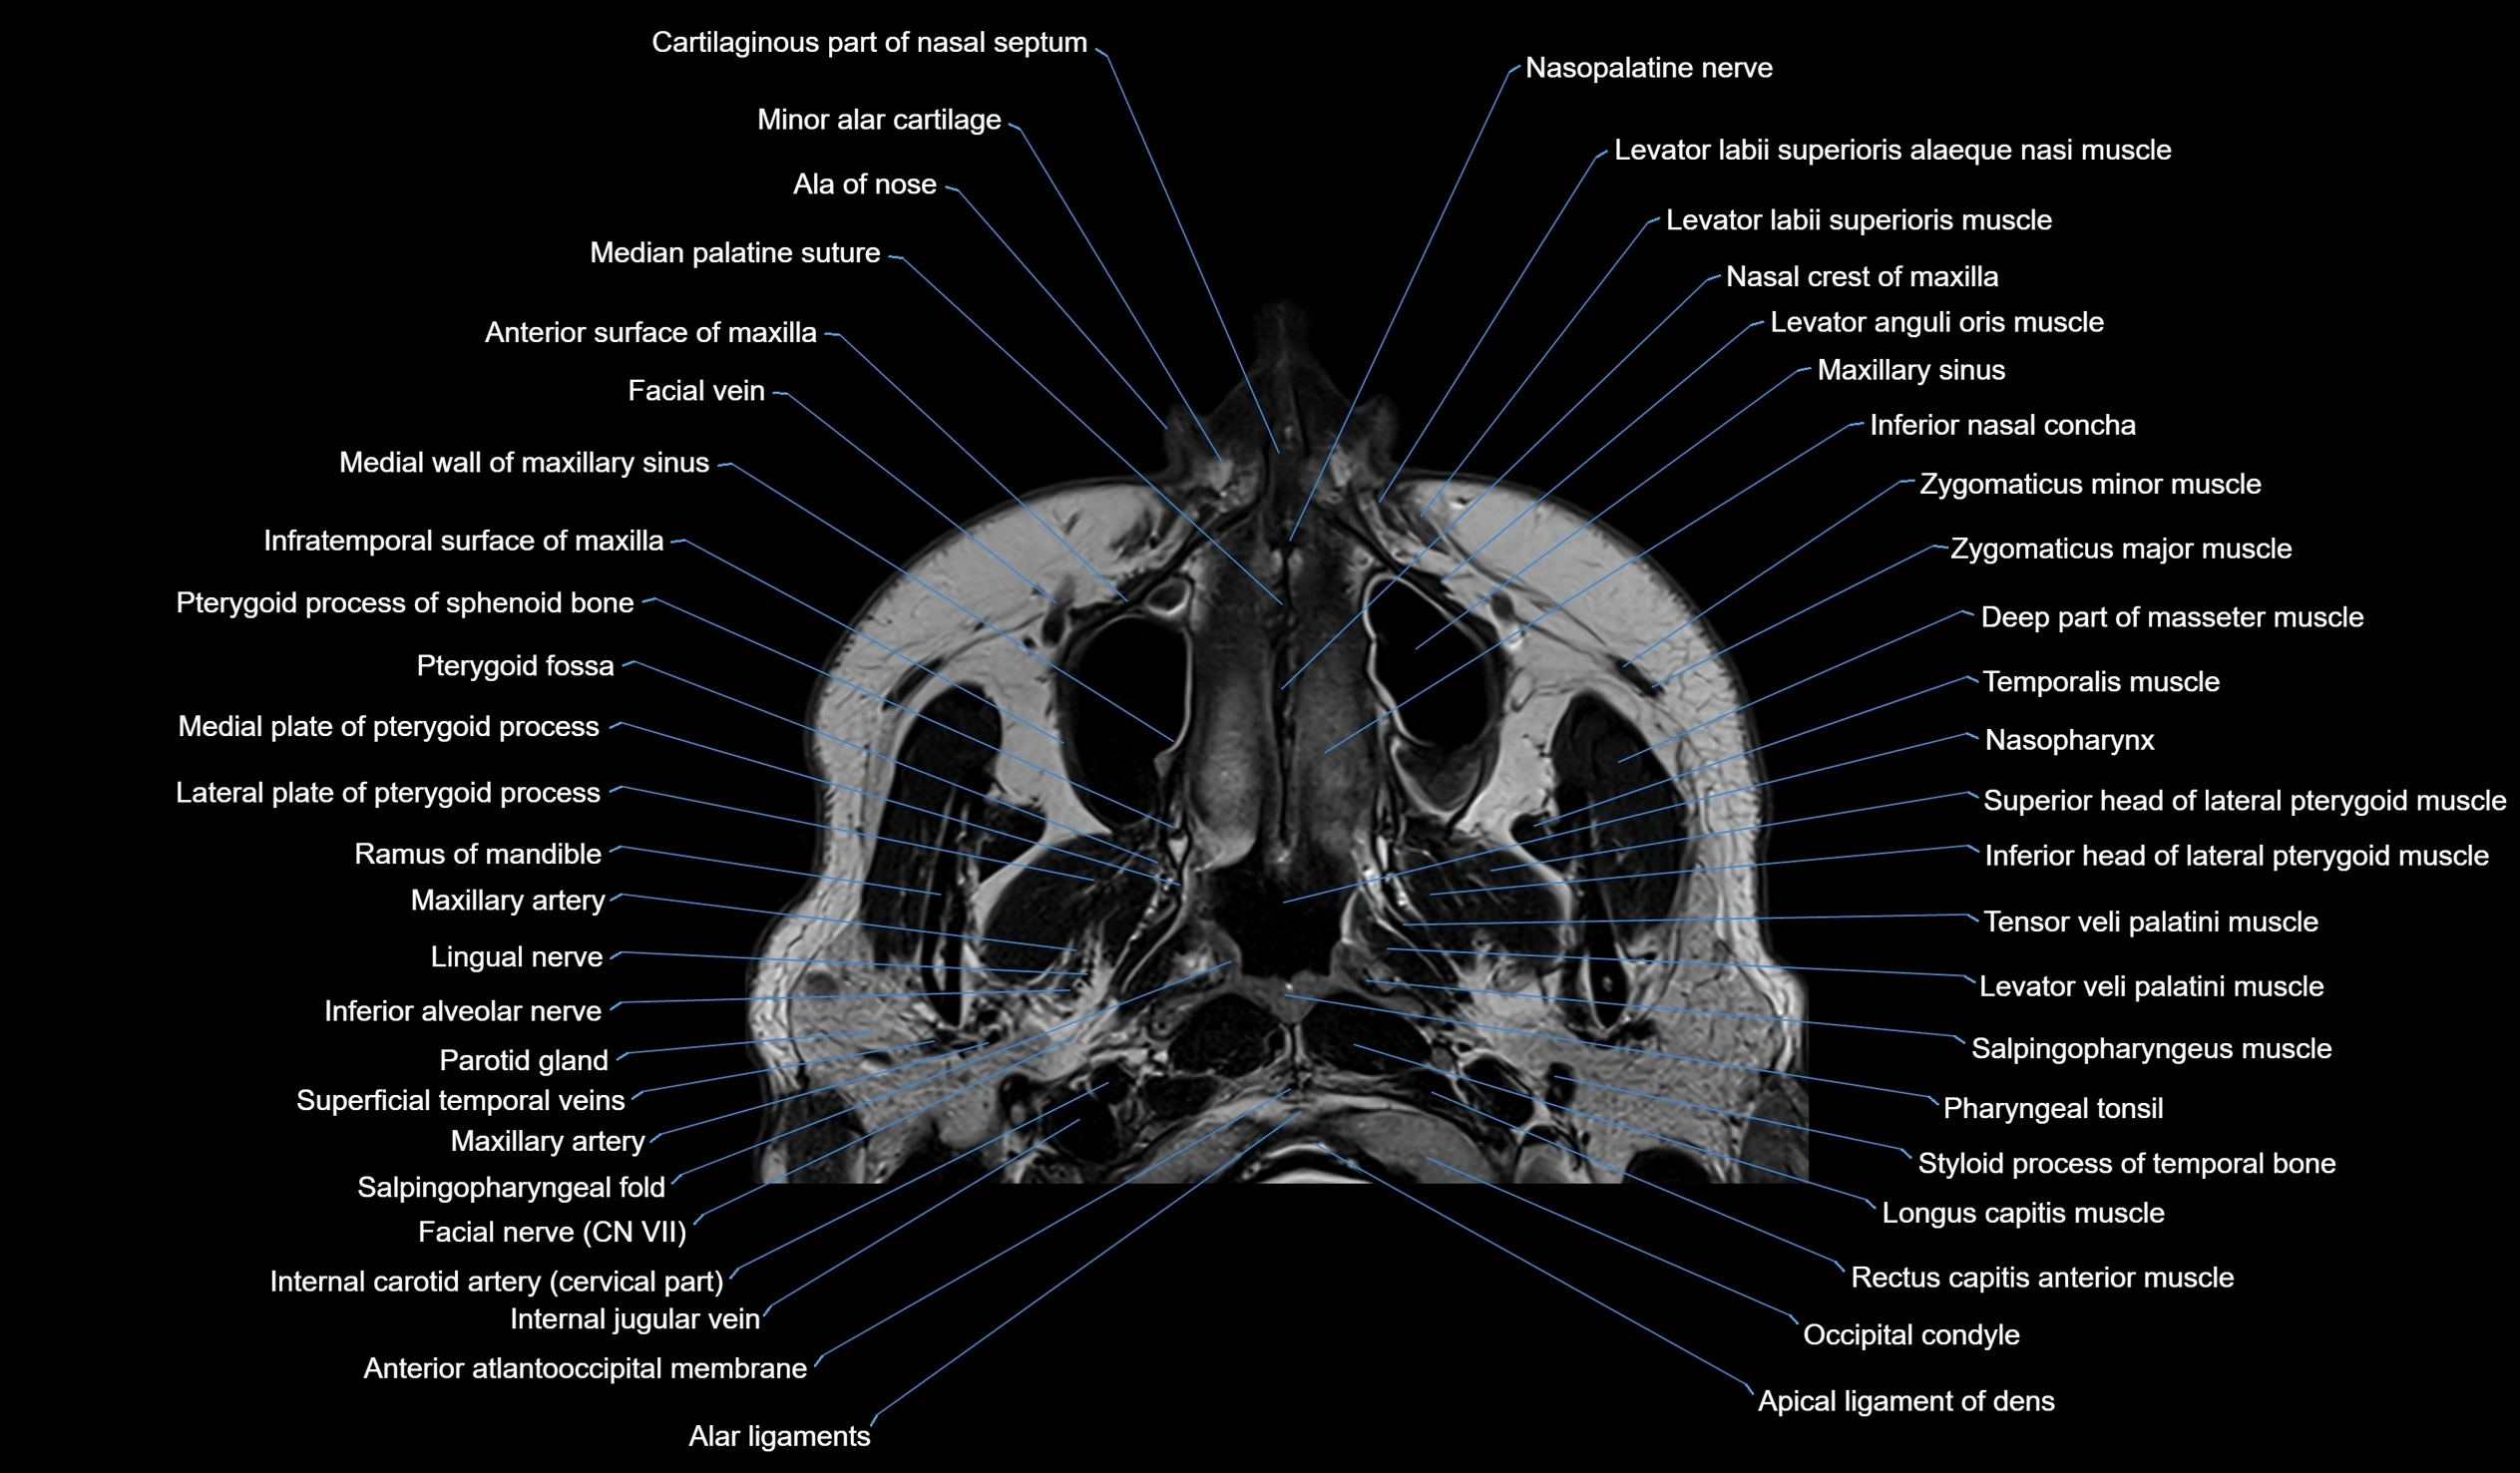

MRI images